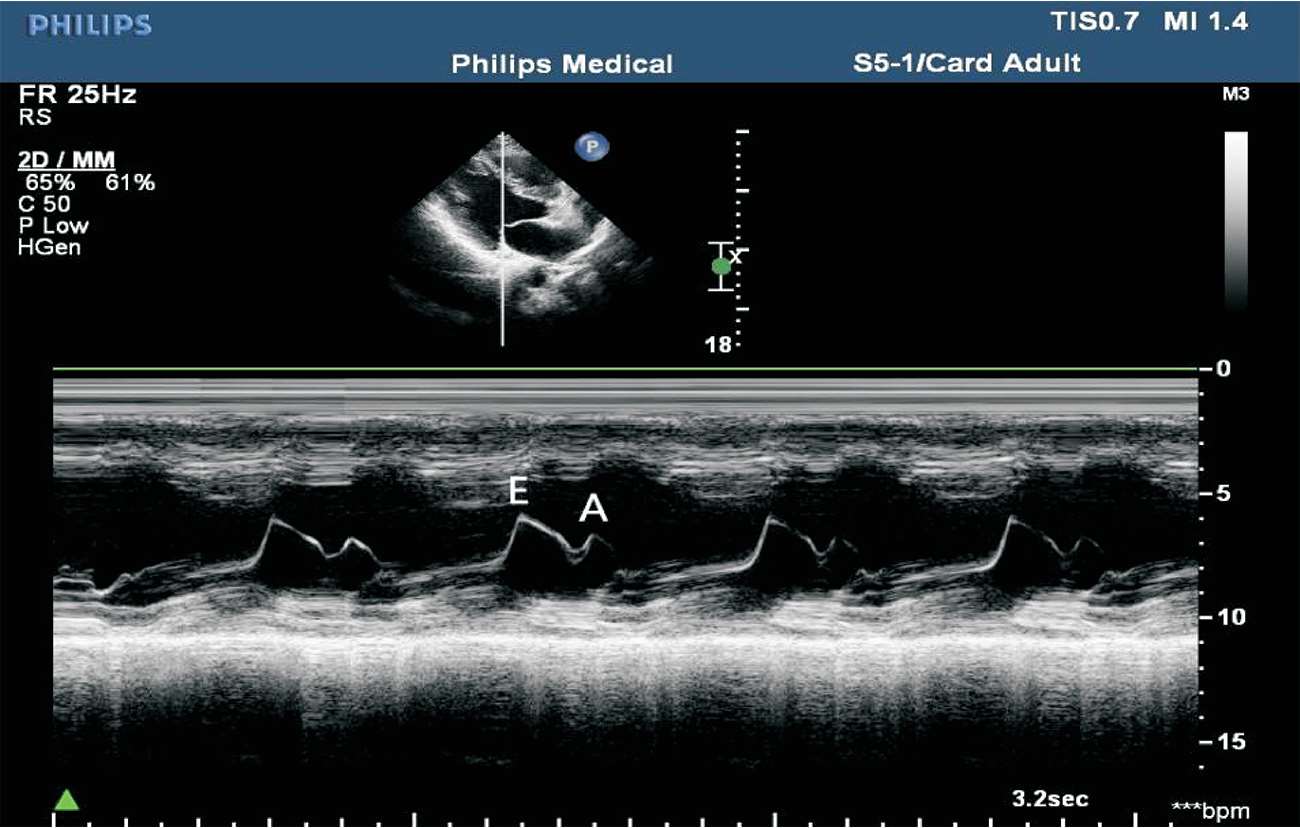

(1)胸骨旁左室长轴切面M型取样线置于二尖瓣瓣尖水平。

(2)结构从前到后依次为右室前壁、右心室、室间隔、二尖瓣前后叶、左室后壁等。

(3)正常二尖瓣前叶曲线为舒张早期E峰和舒张晚期A峰的双峰曲线,而收缩期为一缓慢上升的CD段。

这种双峰曲线具有一定的特异性:A峰位于心电图P波之后,心房收缩推动二尖瓣前叶向前运动。C点位于心电图R波之后,此时心肌收缩,心室压力升高,二尖瓣关闭,产生第一心音。CD段为关闭的二尖瓣随左室后壁的逐渐前移而前移。D点出现于T波与第二心音之后,标准二尖瓣口即将开放。E峰为二尖瓣开放至最大时形成,随后由于左心房排空,左心室充盈,房室间压差迅速减小,二尖瓣前叶曲线迅速下降至F点(见图1-22)。

(4)二尖瓣前后叶活动方向相反,故二尖瓣后叶曲线与前叶曲线相反,呈镜像曲线,为舒张早期E峰和舒张晚期A峰的双峰曲线。收缩期为前后叶合拢形成一起向前的CD段(见图1-23)。